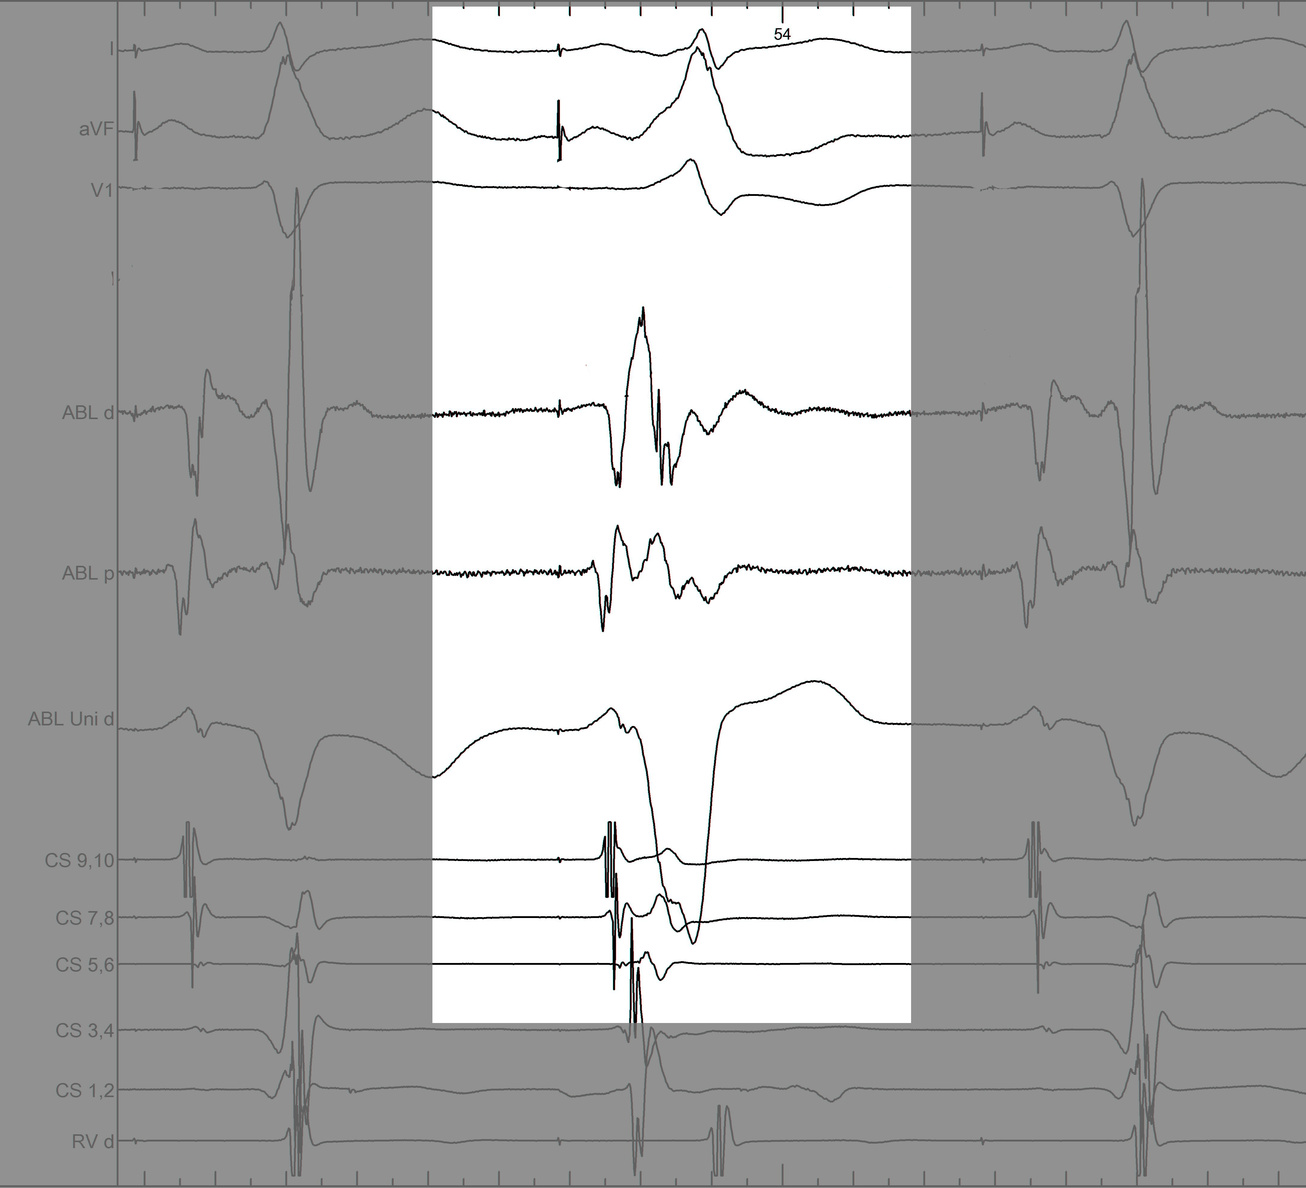

#4 Key to mapping is to identify signal components

mask1.jpg

mask2.jpg

mask3.jpg

mask4.jpg

pseudo_disappearance.jpg